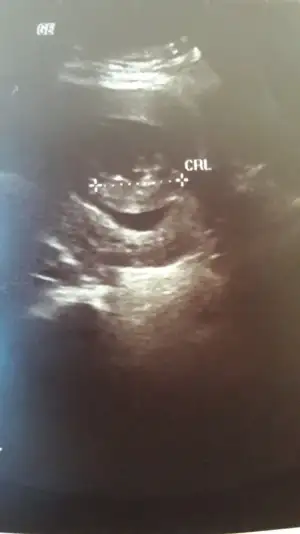

Ikra meyra Ikra meyra 13 haftalık gebelik canım doktor önce erkek dedi sonra kız da olabilir dedi yorumun var mı

Eklentiler

• IMG20210325190828.webp

IMG20210325190828.webp

26,5 KB · Görüntüleme: 87